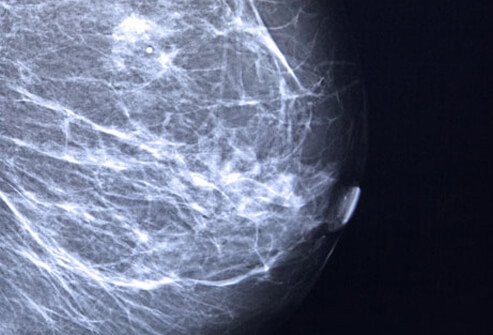

Mammograms and Breast Cancer Prevention

Early detection of breast cancer is the key to survival. Mammograms are X-rays of the breast that can detect tumors at a very early stage, before they would be felt or noticed otherwise. During a mammogram, your breasts are compressed between two firm surfaces to spread out the breast tissue. Then an X-ray captures black-and-white images of your breasts that are displayed on a computer screen and examined by a doctor who looks for signs of cancer. 3D mammograms, or breast tomosynthesis, is a breast imaging procedure that also uses X-rays to produce images of breast tissue in order to detect abnormalities.